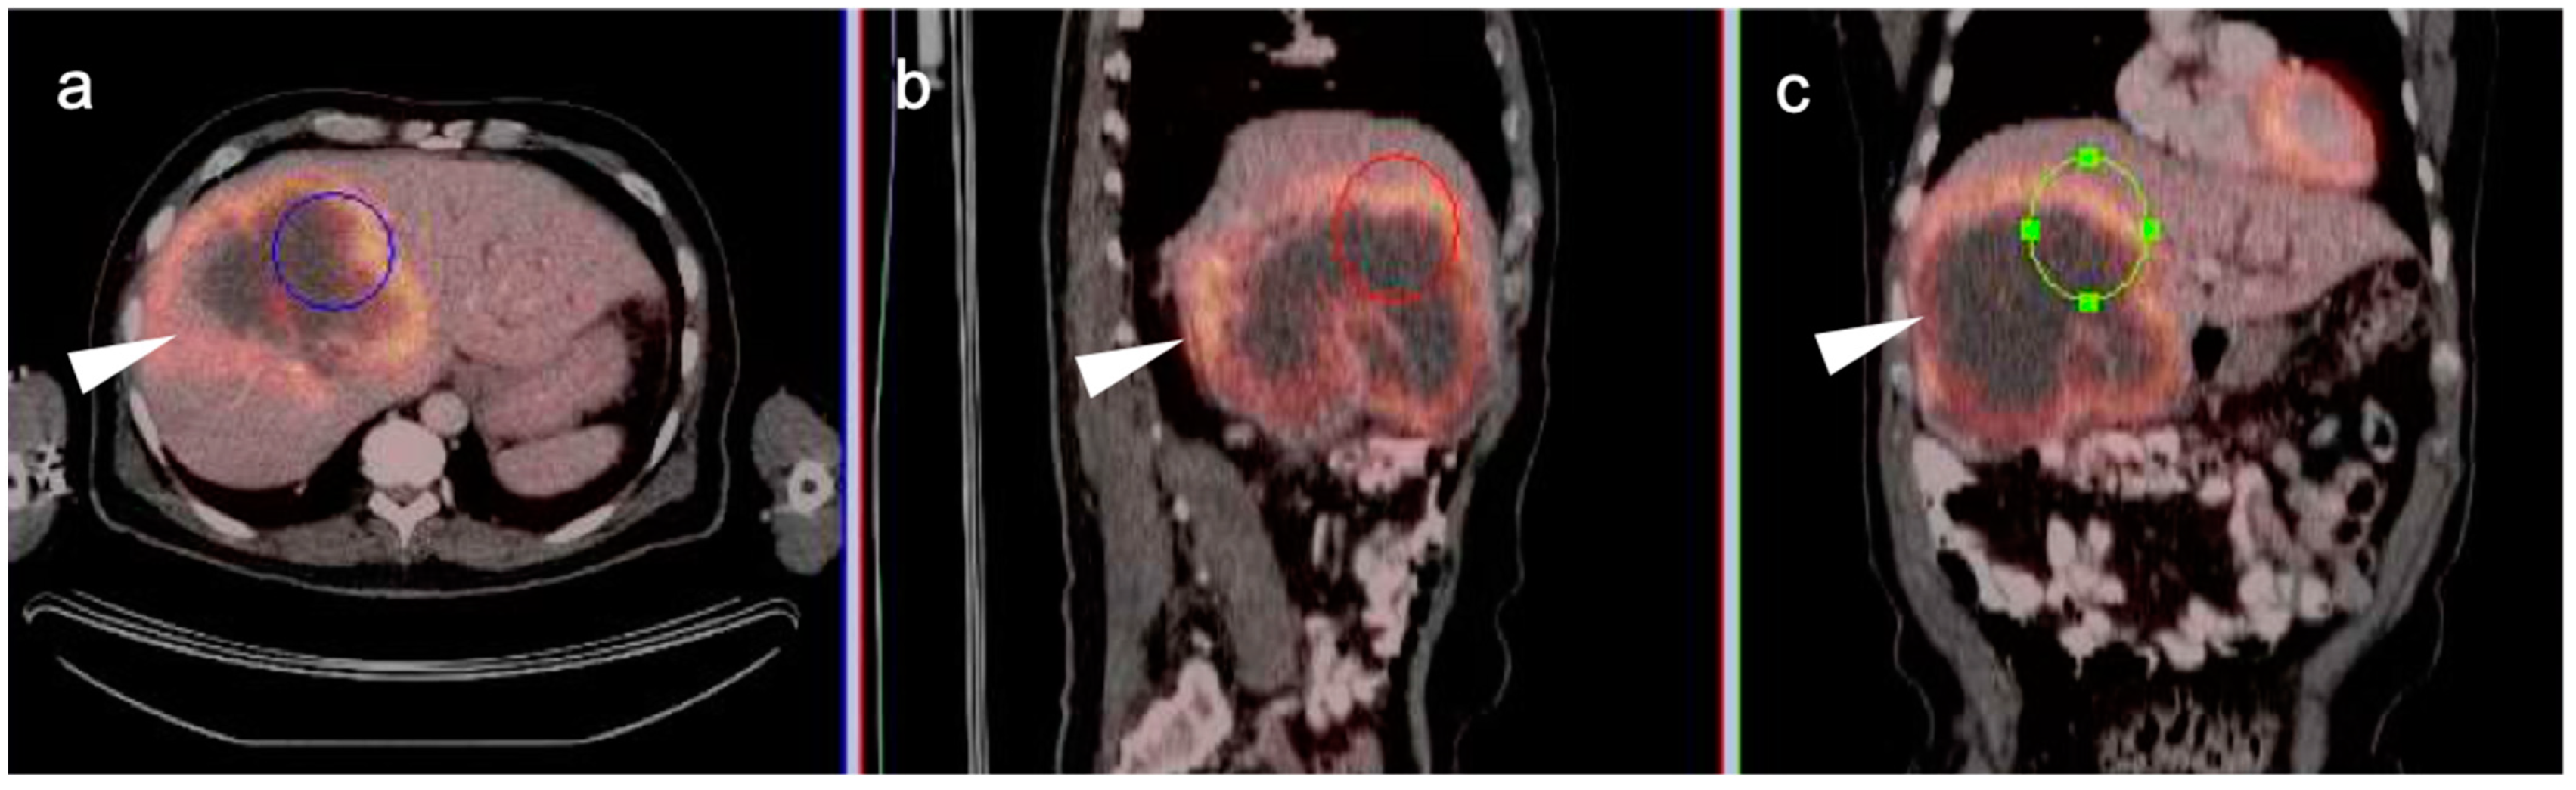

3. Gastrointestinal Stromal Tumor (GIST)

- Van den Abbeele, A.D. The Lessons of GIST—PET and PET/CT: A New Paradigm for Imaging. Oncologist 2008, 13 (Suppl. 2), 8–13. [Google Scholar] [CrossRef]

- Holdsworth, C.H.; Badawi, R.D.; Manola, J.B.; Kijewski, M.F.; Israel, D.A.; Demetri, G.D.; Van den Abbeele, A.D. CT and PET: Early Prognostic Indicators of Response to Imatinib Mesylate in Patients with Gastrointestinal Stromal Tumor. AJR Am. J. Roentgenol. 2007, 189, W324–W330. [Google Scholar] [CrossRef]